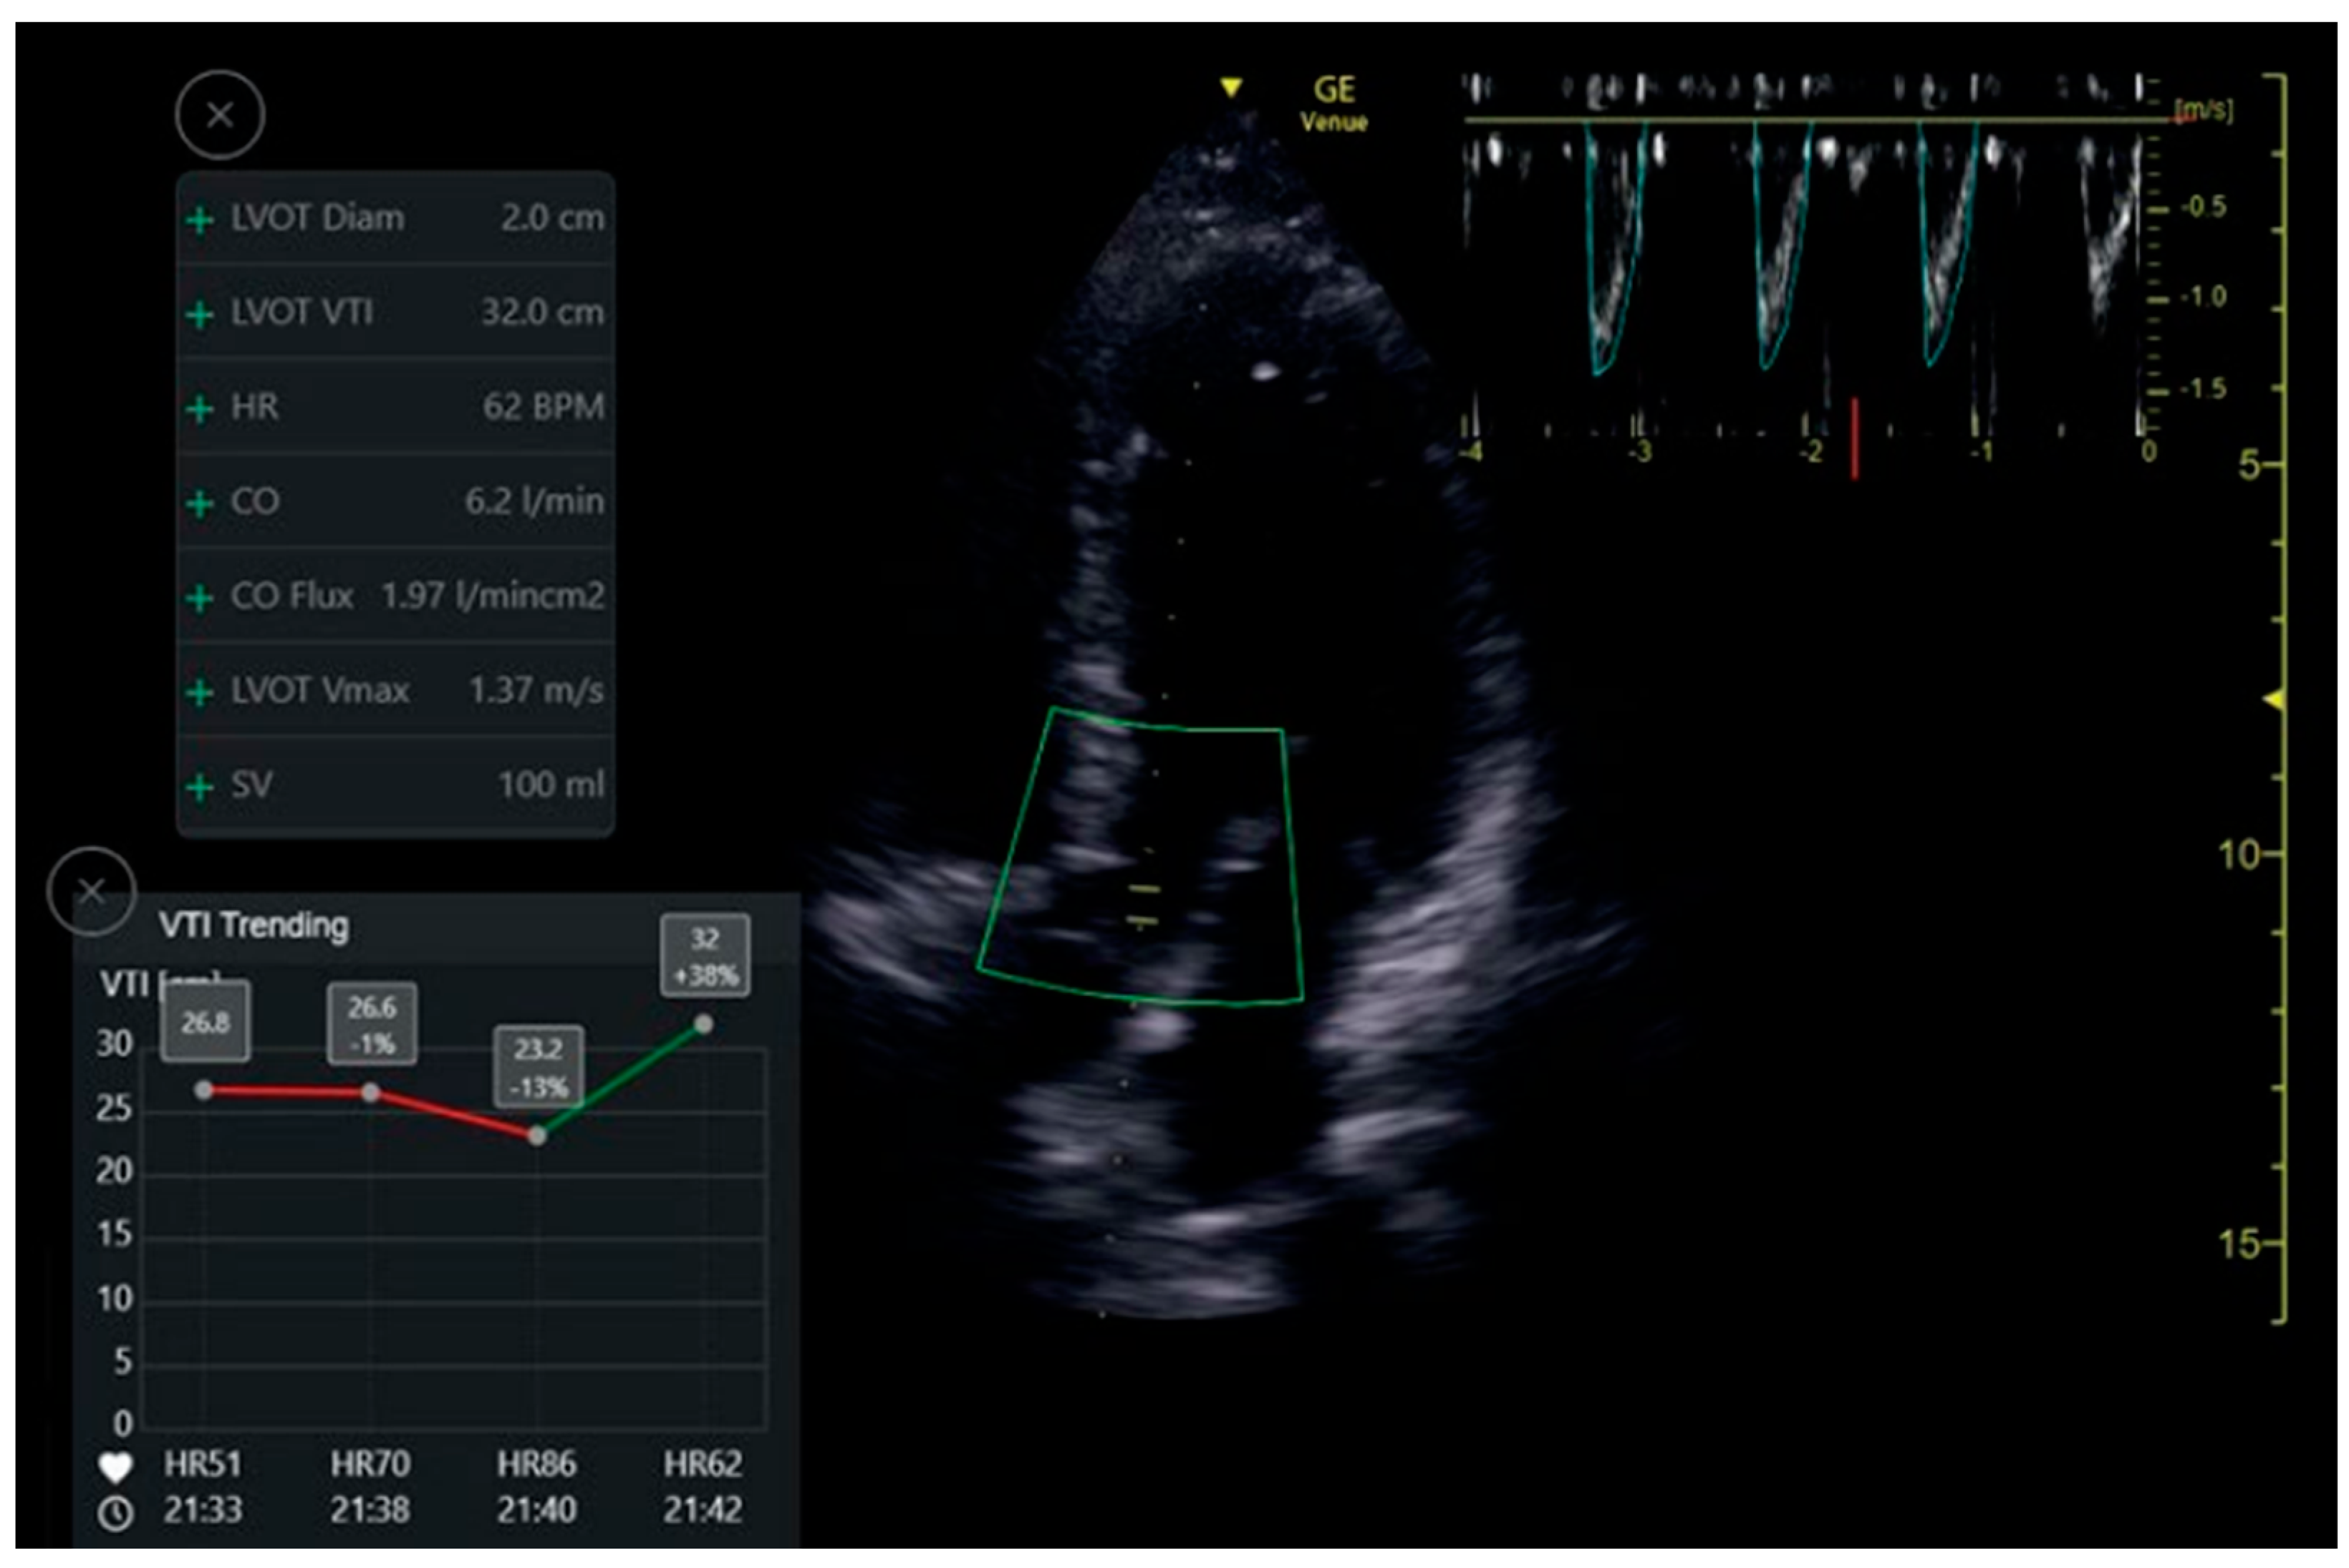

VTI Automatic Measuring Tool

The auto VTI tool is based on proprietary artificial intelligence. The tool automatically places the cursor on the left ventricular outflow tract (LVOT) and auto-traces the velocity waveforms to calculate the VTI. The tool then calculates VTI and CO by averaging all Doppler waveforms during a period of four seconds. Calculations were performed in real-time, and the results are displayed in the Results Box (Figure 5). The Quality Indicator is represented by the color of the curser placed by the system over the LVOT. It varies between green/yellow/red to represent excellent/average/unacceptable image quality, respectively.

7.3. LVOT VTI

One hundred and fourteen apical five-chamber view clips were acquired from 32 patients. The clips were taken in pairs—a POCUS expert acquired a clip, and then without changing the probe position acquired a second, similar clip. Thus, two groups of paired clips were formed. Patients were primarily males (69%), with a mean age of 57.4 ± 18.5 and a mean body mass index (BMI) of 27.1 ± 5.5 (Table 1). When assessed by the Expert, the mean LVOT VTI value was 19.5 ± 4.5 and 17.7 ± 4.3 by the automatic analysis read. The Intraclass Correlation Coefficient for agreement between the automatic and physician-assessed quantifications was 0.825 (95% CI 0.659, 0.905; p < 0.001). In the high clips’ quality subgroup, the Intraclass Correlation was reduced to 0.655 (95% CI 0.013, 0.877; p = 0.024). In the medium clip quality group, the Intraclass Correlation was 0.914 (95% CI −0.077, 0988; p < 0.001) (Table 4). For the image quality agreement, we found a significant difference (p = 0.167, Fishers Exact test value—3.26, α) in the agreement of quality between the physicians’ group and the automatic tools group.

Figure 5. Auto VTI tool. When in Apical5Chamber-View. Auto marker placement, velocity pattern measurements and data display.